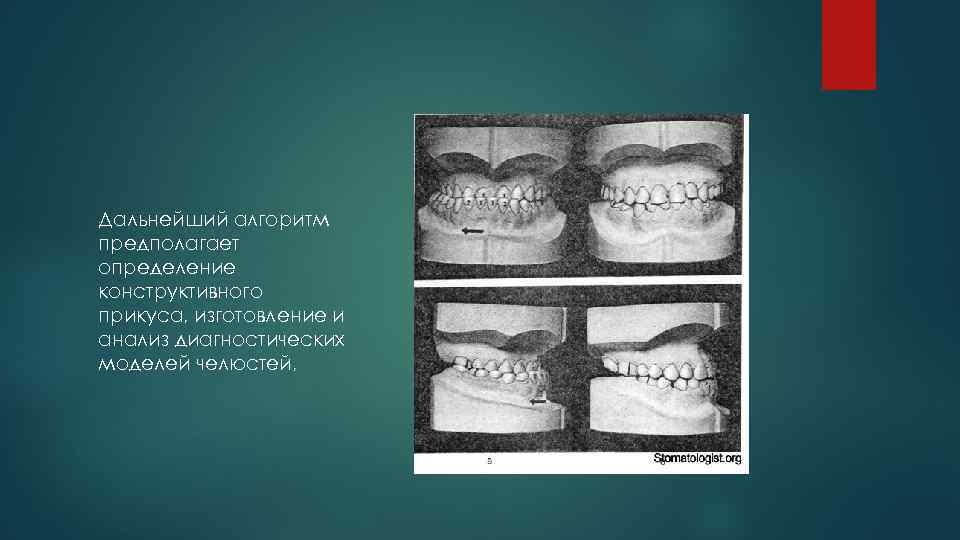

Дальнейший алгоритм предполагает определение конструктивного прикуса, изготовление и анализ диагностических моделей челюстей, .

изучение ортопантомограмм и прямых телерентгенограмм головы.